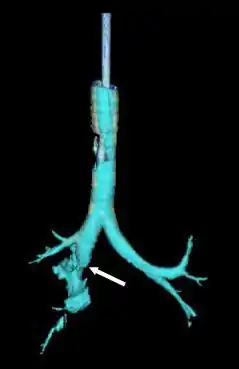

Reconstruction of the trachea and bronchi with x-ray computed tomography showing disruption of the right main bronchus with abnormal lucency (arrow)[1]

Bronchial stenosis (arrow) two weeks after surgery for a tracheobronchial laceration[1]